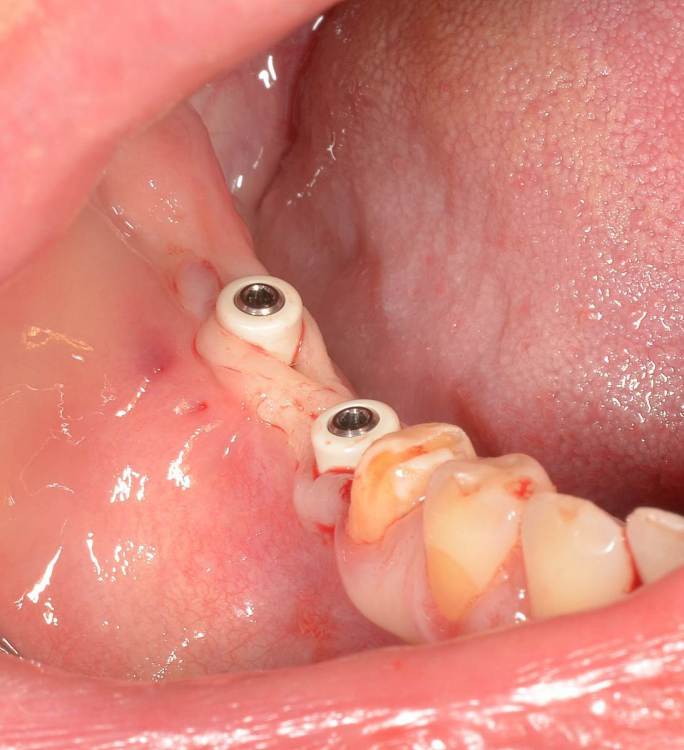

Большой Зеленый Опубликовано 15 августа, 2023 Поделиться Опубликовано 15 августа, 2023 Винтовая фиксация . 8 лет наблюдений .Полет нормальный. Немного прокрасились пломбы в шахтах. Пациентка довольна и счастлива. Привела уже вагон беззубых друзей и родственников. P/S. Система имплантов Ирис...:) 1 Ссылка на комментарий